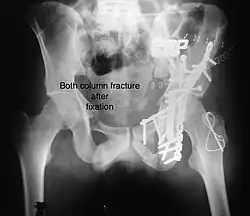

Both column fracture showing floating weight bearing dome -

Both column fracture after fixation with screws and plates -

Combined both column fractures | These are the most complex injuries. Here the weight bearing roof or dome of the acetabulum is a floating piece. This adds to complexity of management.

All three x-ray views plus CT scan is a must for diagnosis and management of this complex injury.

Like any other acetabular fracture, if the femoral head is dislocated out of the socket, early reduction into socket is a priority. However, in this injury, non-operative treatment rarely gives satisfactory results. Surgical management is ideal. The choice of approach rests with the surgeon, but going from front, or anterior approach is must. The posterior injury may be tacked with anterior approach by experienced surgeon. If the patient is unfit to undergo major surgery due to any reason, longitudinal traction to achieve secondary congruence of hip may help to restore hip function, though partially. |